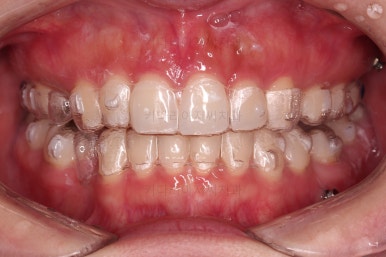

장치 착용 모습인데요.

교정 중임에도 불구하고 거의 눈에 띄지 않는다는 압도적인 장점이 있죠.

공간, 교합, 중앙선 모두 매우 좋아지고 있습니다.

윗니 한 쪽만 왜소치여서 100% 중앙선을 못맞추는 건 환자분 본인도 잘 아시는데요.

그래도 할 수 있는데까지 해보기로 했습니다.